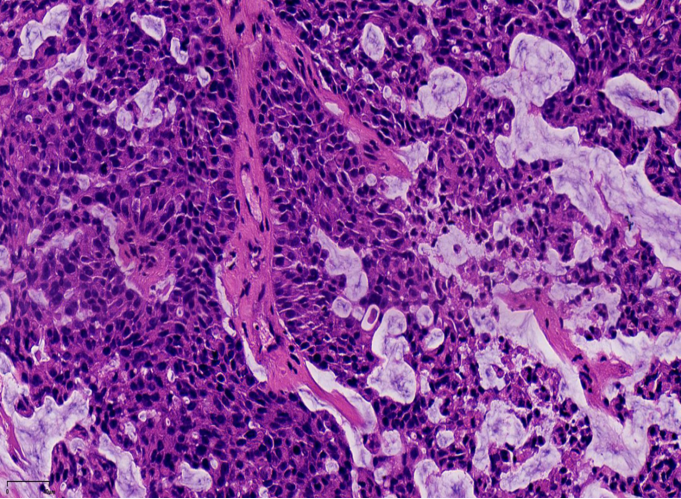

最终诊断:浸润性实性乳头状癌,部分为粘液癌。

1、浸润性实性乳头状癌:保留实性乳头状结构,体积大的团巢,轮廓不规则,间质促纤维反应,肌上皮缺失,原位SPC背景

2、实性乳头状癌伴浸润:轮廓圆滑的结节,伴有浸润性成分,包括粘液癌,NET,浸润性癌(NST)

浸润性SPC

当在原位SPC的背景上,部分原位SPC轮廓变得不规则,或呈地图、锯齿状,并出现促纤维反应,或浸润脂肪,可称为原位SPC伴浸润(毁损性浸润),这时需按浸润癌处理。